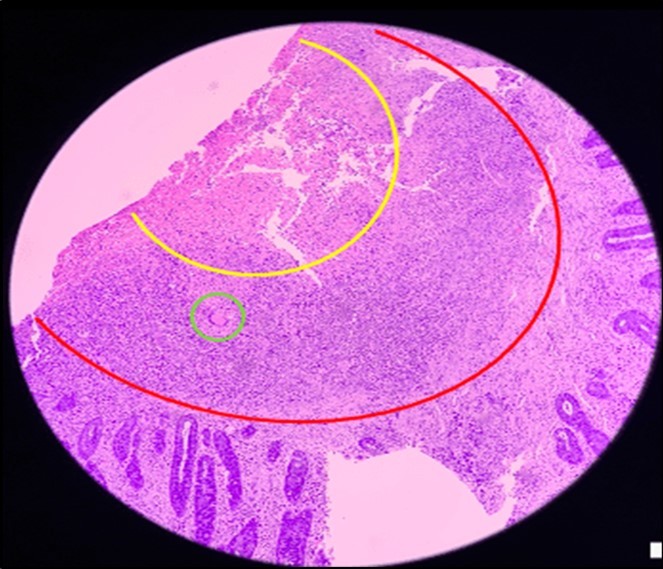

Biopsy showed chronic granulomatous inflammation with caseation necrosis and Langhan’s type giant cells consistent with tuberculous etiology (Figure 6, and Figure 7). TB PCR detected Mycobacterium tuberculosis, Rifampicin (MTB, RIF) resistance indeterminate. Category I Anti-TB treatment for six months was started and the service planned to repeat both colonoscopy and CT-scan after the initial round of anti-TB treatment. Currently, the patient is able to work with no abdominal pain and was able to tolerate her anti-TB drug regimen

Figure 6.Pathologic slide in the low power field. The area inside the yellow circle is the area of central necrosis. The portion inside the red circle is the peripheral lymphocytic ring, and inside the green circle is the Langhan’s type multinucleated giant cells